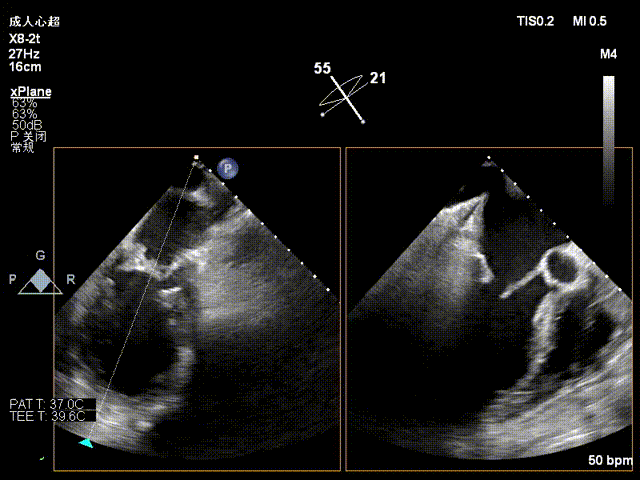

1.术前超声提示双房增大,四腔心切面左房大小约77*65mm,右房大小约41*59mm;2.二尖瓣瓣叶稍厚,回声增粗增强,开放可,关闭不佳,关闭时二尖瓣后叶(P2区及部分P3区)脱垂伴重度关闭不全;3.主瓣、三尖瓣少量反流。

术前二尖瓣大量反流,脱垂宽度超过20mm,主要为P2区及部分P3区

手术经股静脉-房间隔入路,采用全身麻醉插管,在TEE和DSA引导下完成房间隔穿刺。置入JensClip瓣膜夹系统后,在左房调整瓣膜夹的位置和轴向,后进入左室,在TEE引导下捕捉二尖瓣前后瓣叶,并关闭瓣膜夹。经TEE反复确认手术效果后最终锁定并释放瓣膜夹。由于该病例二尖瓣后叶P2区及部分P3区脱垂,脱垂范围宽度达20mm,术中植入了两枚长宽(LW)的瓣膜夹。术后即刻超声显示瓣膜夹位置稳定,功能良好,二尖瓣反流由术前4+减少至微量,肺静脉逆流和左房压都显著好转,手术圆满成功。术后患者状态良好,目前已安排出院。